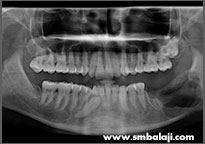

X-ray showing 6 impacted teeth- upper right and left third molars and lower right and left third and second molars